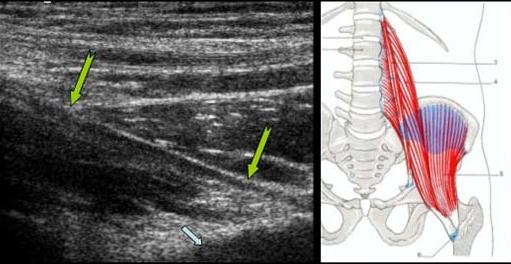

TENDINOPATIE

CALCIFIANTA

A TENDONULUI DIRECT AL MUSCHIULUI DREPT FEMURAL

Insertia tendonului direct al m. drept femural

pe spina Iliaca

antero inferioara →

Tendonul este ingrosat, hipoecogen →

cu mici calcificari →